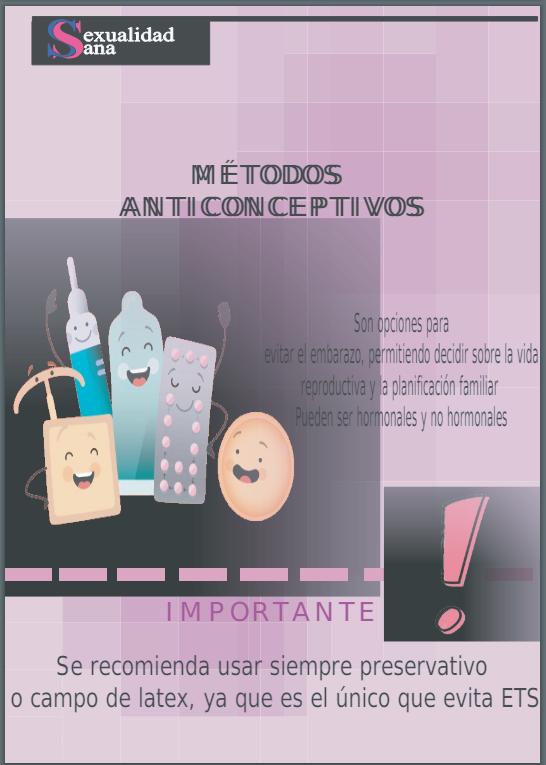

7. MÉTODOSANTICONCEPTIVOS

7.1. Tipos de métodos anticonceptivos

7.1.1.Métodos de barrera

También se lo conoce como método contraceptivo es aquel que impide, minimiza o reduce significativamente las posibilidades de una fecundación en mujeres fértiles que mantiene relaciones sexuales de carácter heterosexual.

Pues esto contribuyen decisivamente en la toma de decisiones sobre el control de la natalidad (número de hijos que se desean o no tener), la prevención de embarazos, así como en la disminución del número de embarazos no deseados y embarazos en adolescentes. Los métodos que se administran después de mantener relaciones sexuales se denominan anticonceptivos de emergencia

Los métodos anticonceptivos son técnicas y dispositivos que se utilizan para prevenir el embarazo. Existen diversas opciones, cada una con sus propias ventajas, desventajas y niveles de eficacia.

Los métodos anticonceptivos permiten a las personas planificar y espaciar sus embarazos, lo que contribuye a una mejor salud materna e infantil.

Cada método tiene una eficacia diferente y puede tener efectos secundarios. La elección del método más adecuado depende de factores individuales como la salud general, la frecuencia de las relaciones sexuales.

El número de parejas sexuales y las preferencias personales. Es importante consultar con un profesional de la salud para tomar una decisión informada.

Esto ayuda a evitar embarazos no planificados que pueden tener consecuencias negativas tanto para la madre como para el niño..